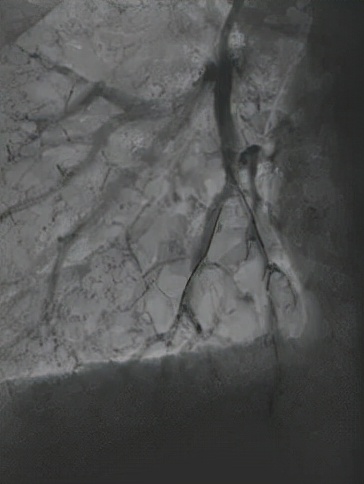

△球囊擴張後複查,血管血流明顯改善

“人體的肺血管如同一棵大樹,血栓常常堵在了‘樹杈’、‘分支’部位,對狹窄血管進行擴張疏通,可以顯著緩解肺動脈壓力、血管阻力等問題。”介入手術過程中,醫生需要身著厚重的防輻射鉛衣,屏氣凝神,在細微的血管間謹慎地完成每一項精細的操作,“如果稍有不慎,非常容易導致血管破裂,造成嚴重的併發症,非常考驗操作者的經驗與熟練度。”洪城副主任醫師說,他們一次性為患者開通了8條血管,肺血管灌注後血流明顯好轉。